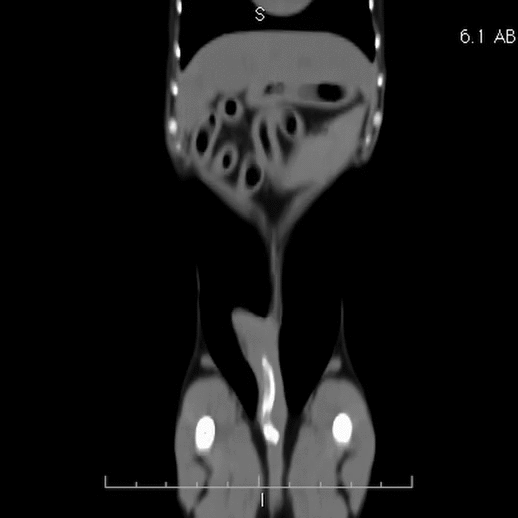

Comme la majorité d’entres vous le recommandiez, nous avons échographié l’abdomen de ce chien sans toutefois arriver à identifier le corps étranger (flèche jaune). Il faut toutefois préciser que l’estomac était légèrement dilaté par de l’air, tout comme le côlon transverse qui le longe tout juste caudalement. Il n’y avait pas de signe de perforation (air libre ou épanchement liquidien). Cependant, les gras étaient hyperéchogènes tout près du caecum qui se trouvait sous l’arche costale du côté droit. En raison de la minceur du corps étranger et pour éviter une longue chirurgie exploratrice possiblement non fructueuse, une tomodensitométrie (CT-scan) a été proposée pour en déterminer la localisation. Sur les images reformatées en différents plans (voir ci-bas), le corps étranger a été localisé dans les gras tout juste derrière le corps de l’estomac. Fait intéressant, il n’y avait pas d’air libre dans la cavité péritonéale. Ces informations ont permis au chirurgien de rapidement identifier le petit fil de métal en palpant doucement les gras derrière l’estomac. Le petit corps étranger n’était pas visible à l’oeil nu et aurait probablement été difficile à trouver sans l’aide du CT. On spécule que le petit fil de métal provenait d’une brosse à BBQ. Comme quoi il faut savoir brosser avec modération !